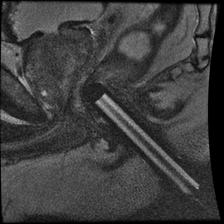

Here is an example of 61 year old man who had rising PSA and negative transrectal prostate biopsies. The patient had five prior transrectal ultrasound biopsies with estimated 51 cores obtained over multiple years:

Figure 4: Following the diagnostic MRI he underwent a MRI Guided prostate biopsy where only 2 cores were obtained through the left sided suspicious region in the prostate gland.

MR guided prostate biopsy-2cores revealed an intermediate risk prostate cancer with Gleason Grade 7 (4+3)